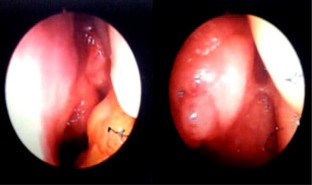

Primary localized amyloidosis in the head and neck region is a rare entity. The most commonly involved organ is larynx. Primary amyloidosis localized to the sinonasal tract is extremely rare. We report one such case along with a brief review of the associated literature. The aim of reporting this case is to emphasize the fact that sometimes nasal amyloidosis can also present with signs and symptoms of nasal and nasopharyngeal malignancy. The definitive diagnosis in such cases depends upon histopathology and further confirmed by immunohistochemistry. A 55-year old male presented with recurrent episodes of nasal bleed, bilateral nasal obstruction, and bilateral hearing loss from last 7 years. On clinical examination a mass was found in the nasal cavity on both sides reaching up to the nasopharynx. Contrast enhanced CT scan revealed that the mass was extending up to the skull base and destroying bony landmarks of the nasal cavity and paranasal sinuses. Mass was proved to be amyloidosis after histopathological examination. It showed multiple blotches of globular submucosal deposit of amyloid, on staining with Congo red. Immunohistochemistry confirmed AL amyloidosis with expression of mixed kappa and lambda light chain immunoglobulin (κ > λ). No evidence of systemic amyloidosis was found after proper work up. It was managed by conservative surgery.